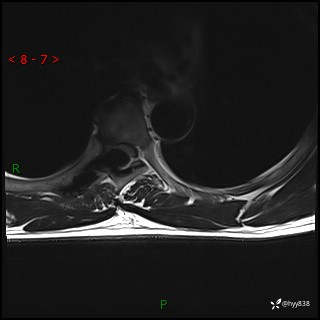

axi T2WI